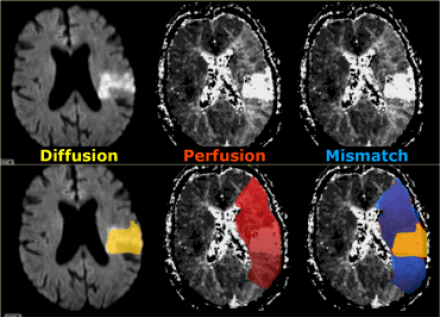

МРТ перфузия.

Перфузия на МРТ сопоставима с КТ-перфузией. При МР-перфузии используется болюс с контрастным веществом Gd-DTPA. Т2 последовательности более чувствительны к изменению сигнала, поэтому используются для МР-перфузии.

Зона с дефектом перфузии является безвозвратно ишемизированной тканью или зоной пенумбры (ткань риска). При комбинировании диффузно-взвешенного изображения и перфузии есть возможность отдифференцировать зоны пенумбры и зоны безвозвратной ишемии.

На нижележащих изображениях слева представлена диффузно-взвешенное изображение, на котором возможно выявить ишемизированную ткань. Среднее изображение соответствует мр- перфузии, на котором визуализируется огромная область гипоперфузии. На крайне правом изображении diffusion-perfusion mismatch визуализируется зона ткани-риска, которая отмечена синим и возможно будет сохранена после терапии.